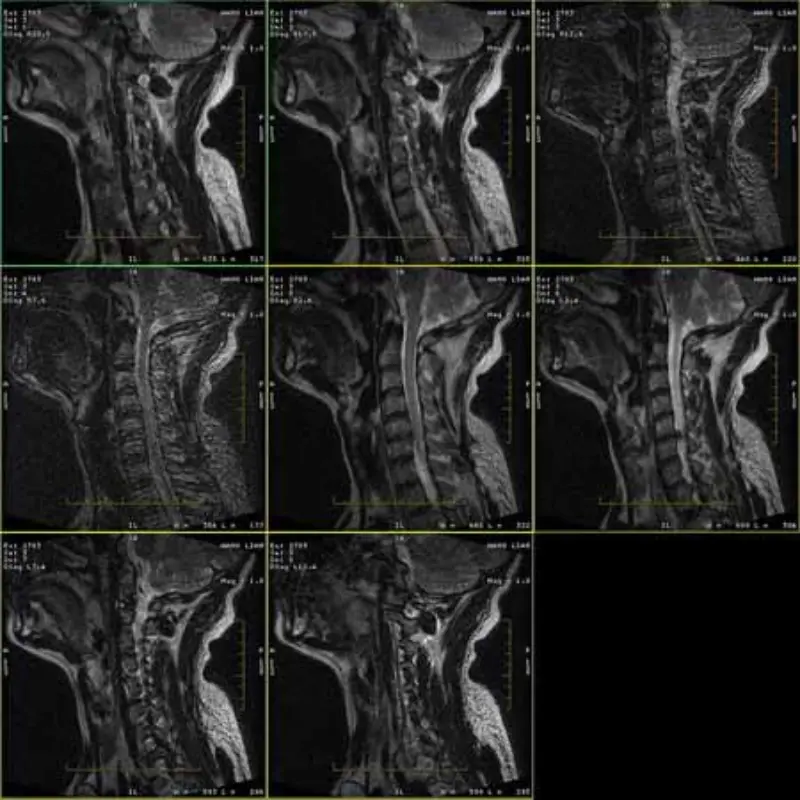

Die Bilder der FRFSE- und GRE-Protokolle weisen Geisterbilder auf und manchmal erscheinen Bilder mit niedrigem SNR in einer Serie. Aber SE-Protokollbilder sind normal.

Bitte schauen Sie sich die Bilder an.